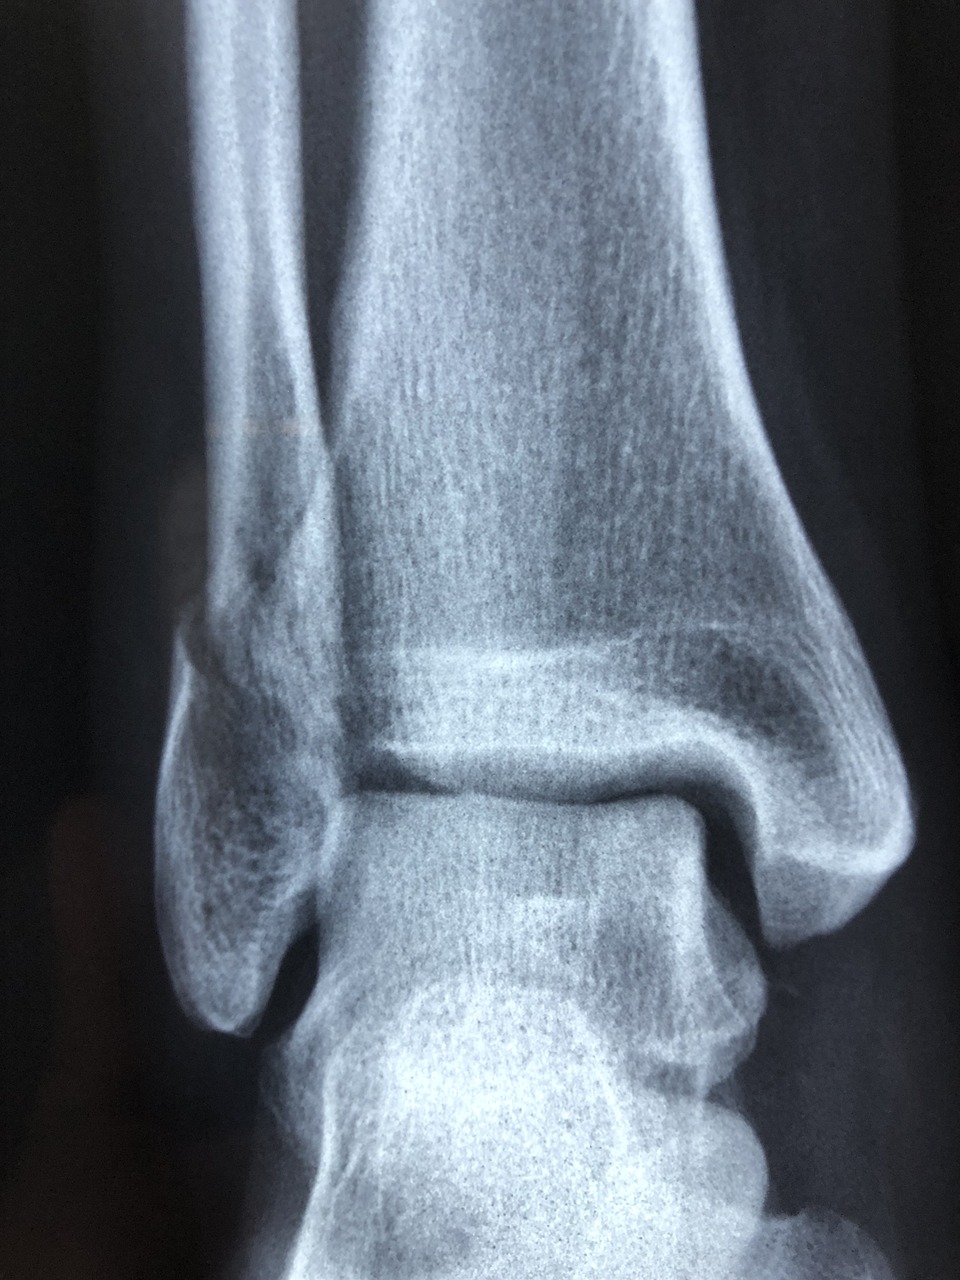

골절은 뼈가 부러지는 상태로, 이는 특히 충격이나 강한 외상에 의해 발생합니다. 골절이 발생하면 적절한 치료 및 재활이 필요하며, 영양도 이러한 과정에서 중요한 역할을 합니다. 골절 치유 및 뼈의 건강을 지원하기 위해 다양한 영양소를 고려하는 것이 중요합니다. 골절에 좋은 음식과 피해야 할 음식에 대해서 알아보겠습니다.